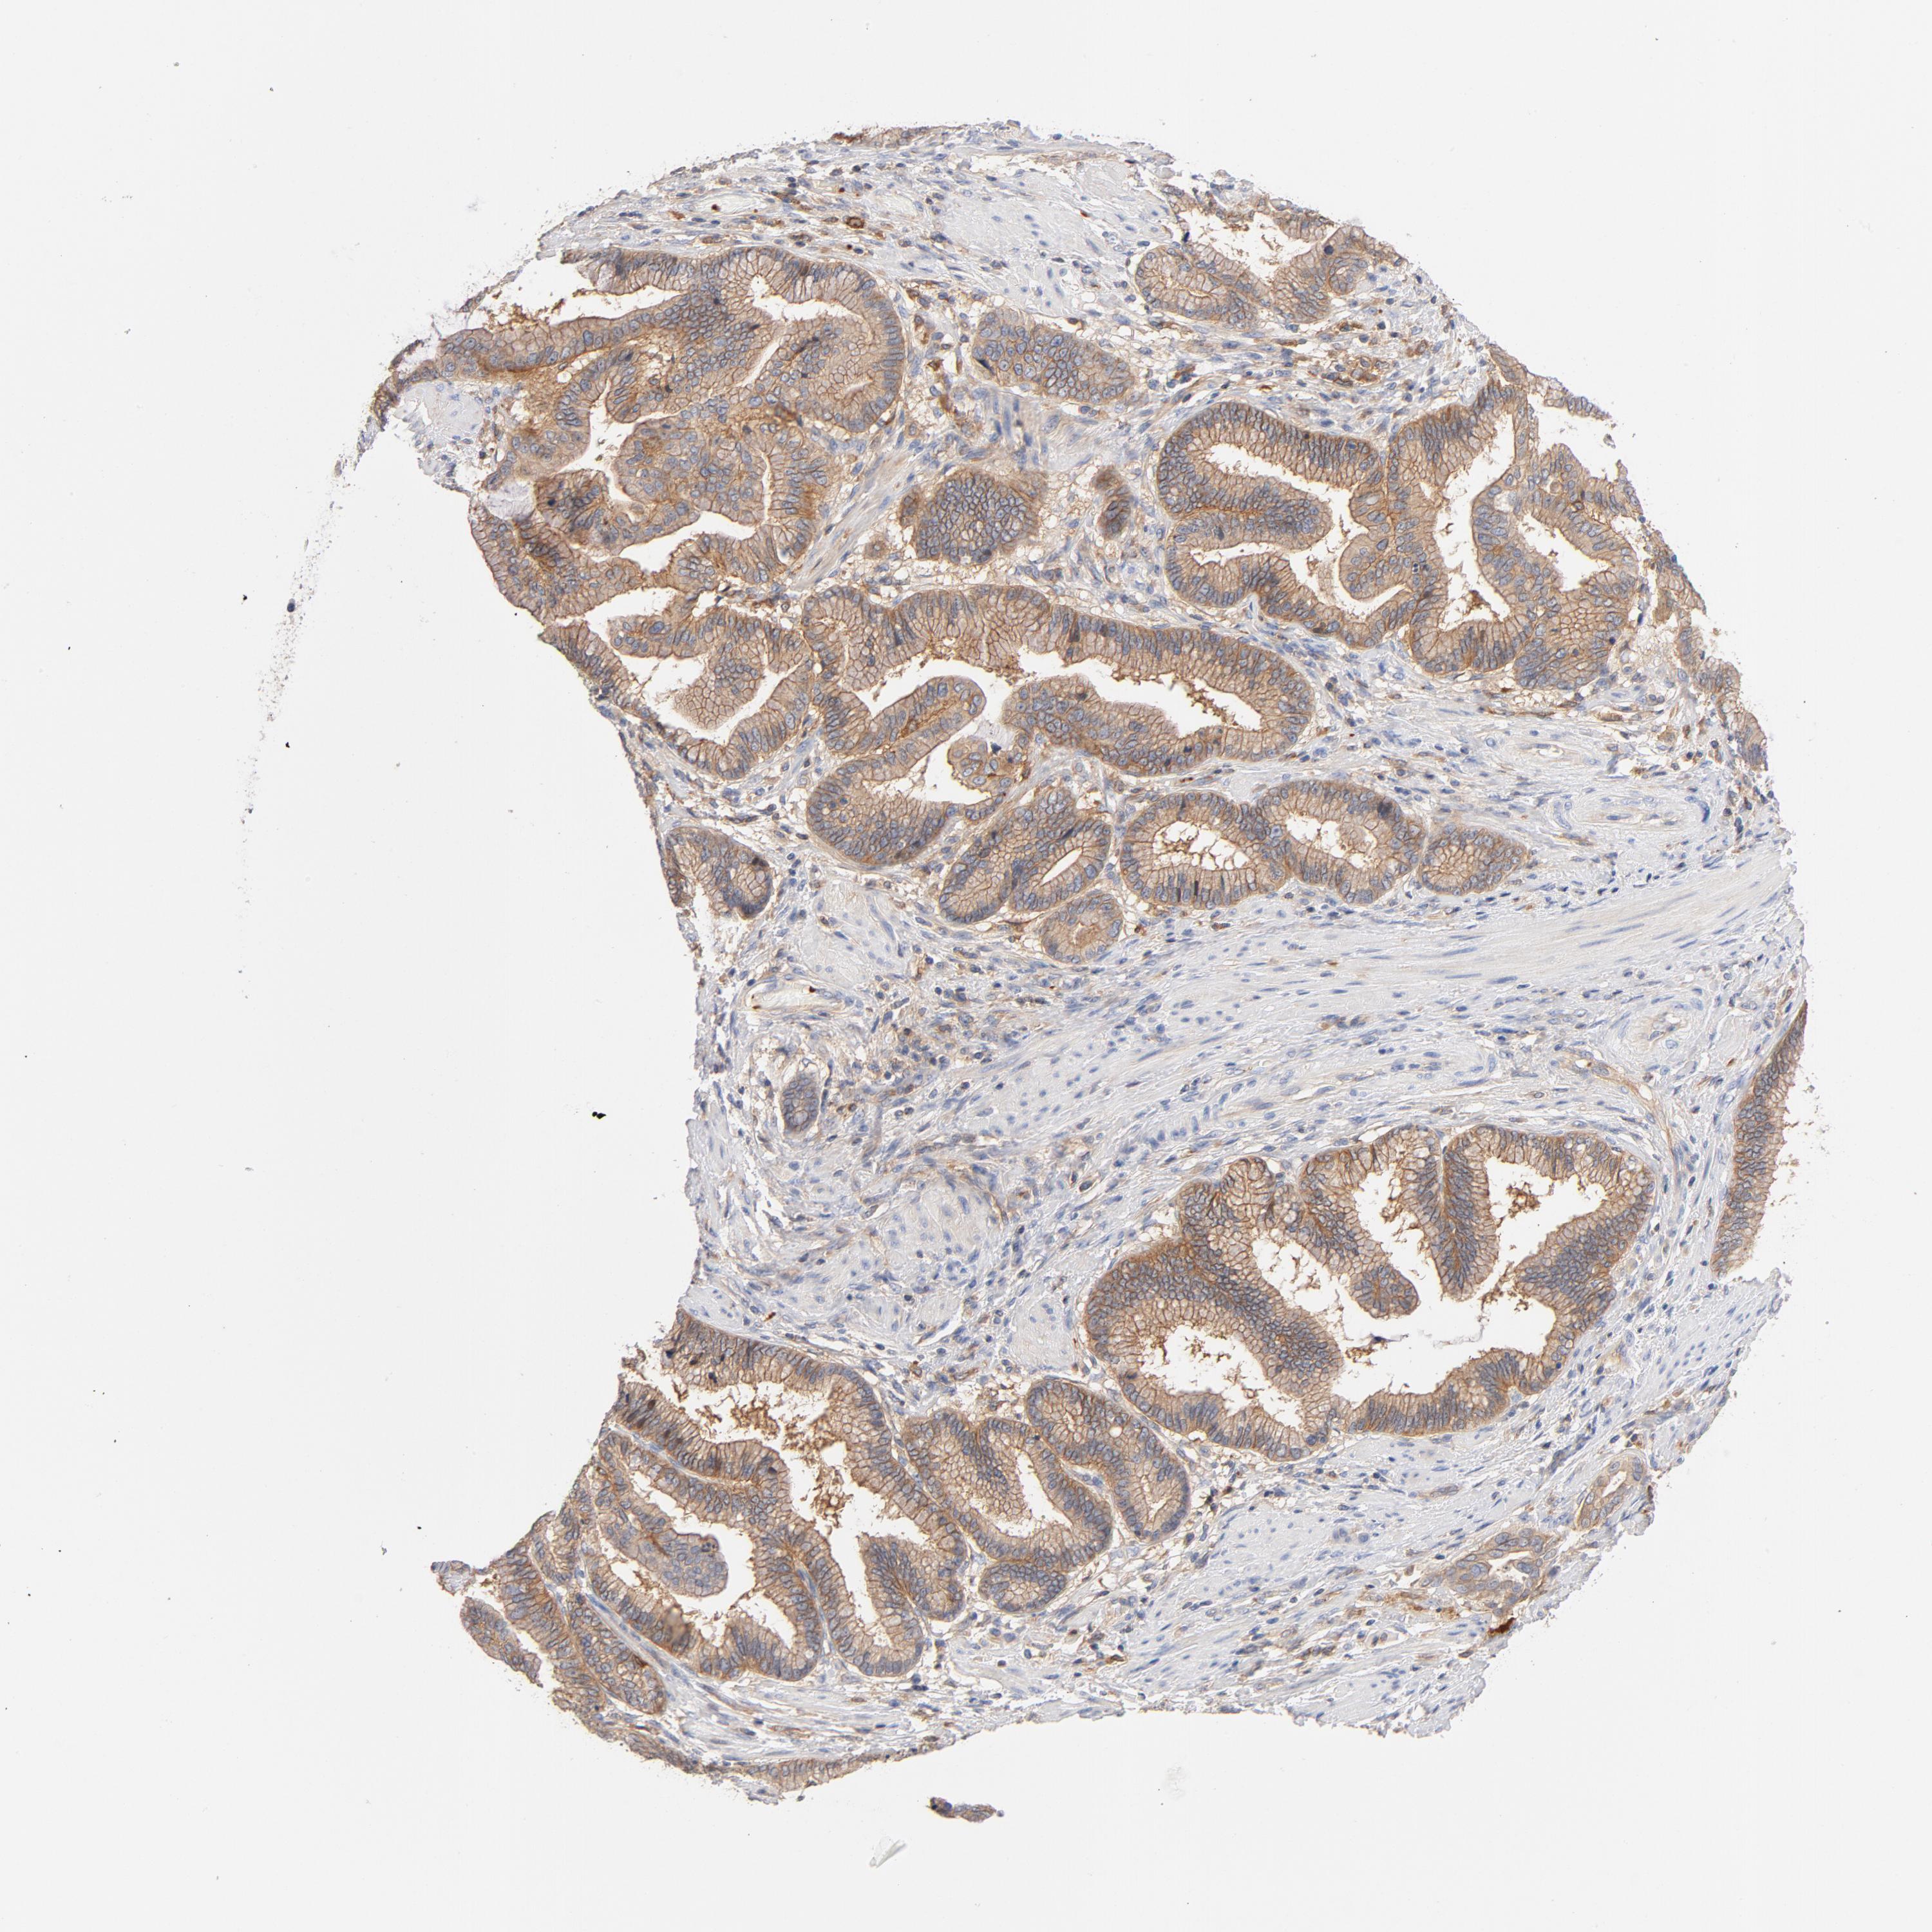

PANCREATIC CANCER - Protein expressioni

A mouse-over function shows sample information and annotation data. Click on an image to view it in a full screen mode. Samples can be filtered based on level of antibody staining by selecting one or several of the following categories: high, medium, low and not detected. The assay and annotation is described here.

Note that samples used for immunohistochemistry by the Human Protein Atlas do not correspond to samples in the TCGA dataset.

Antibody stainingi

Antibody staining in the annotated cell types in the current human tissue is reported as not detected, low, medium, or high, based on conventional immunohistochemistry profiling in selected tissues. This score is based on the combination of the staining intensity and fraction of stained cells.

Each image is clickable and will lead to virtual microscopy that enables deeper exploration of all samples and also displays staining intensity scores, fraction scores and subcellular localization as well as patient and tissue information for each sample.

Antibody HPA030875

Antibody CAB004023

Staining

High

Medium

Low

Not detected

Intensity

Strong

Moderate

Weak

Negative

Quantity

>75%

75%-25%

<25%

None

Location

Nuclear

Cytoplasmic/membranous

Cytoplasmic/membranous,nuclear

Adenocarcinoma, NOS

Adenocarcinoma, metastatic, NOS